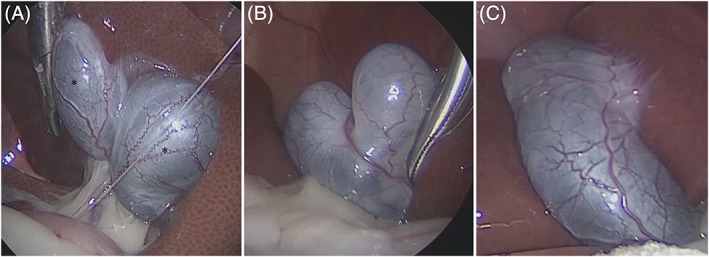

Cats were fasted for at least 12 hours and sedated using a mixture of midazolam at a dosage of 0.2 mg/kg and butorphanol at a dosage of 0.2 mg/kg administered IV. Propofol at a dosage of 0.5 mg/kg was administered IV to effect, followed by tracheal intubation to maintain anesthesia using 100% O2 and isoflurane inhalation. After laparoscopic ovariohysterectomy, we recorded the morphology from the gallbladder to the CBD. Then, a needle (23 G, 11/4 inch) was inserted aseptically into the gallbladder to collect bile (Figure 1). The color of the collected bile was recorded, the volume and AMY and LIPA activity of the bile were measured, and aerobic and anaerobic bacterial culture and identification were performed at the same time.

Laparoscopy indicated that the main site of tortuosity was the CD. Furthermore, the junction of the CBD and the hepatic duct was not visually distinct because of fat adhering to the biliary tract. The CBDs that could be confirmed by laparoscopy were nearly straight. In contrast, several different morphologies were observed for the CD, depending on the extent of dilatation and tortuosity. Moreover, the more severe the dilatation of the CD, the more distinct the morphology (Figure 3). Therefore, differences in the extent of CD dilatation appear to be a factor in the formation of distinctive biliary system morphologies in cats.

Three types of gallbladder morphology were observed: double gallbladder (1 cat, Figure 4A), bilobed (heart‐shaped) gallbladder (7 cats, Figure 4B), and normal (oval‐shaped) gallbladder (44 cats, Figure 4C). Thus, the frequency of gallbladder malformation in our study was 15.3% (8/52 cats).

In addition, only 1 cat had markedly high bile AMY and LIPA activity (bile AMY, 591 U/L; bile LIPA, 754 U/L; serum AMY, 1378 U/L; serum LIPA, 25 U/L). The bile sample from this cat was light brown in color and 4.5 mL in volume, the largest volume in the study. The CD/CBD ratio in this cat was 7.4 (group B) and uniform dilatation from the CD to the CBD was observed (Figure 7).